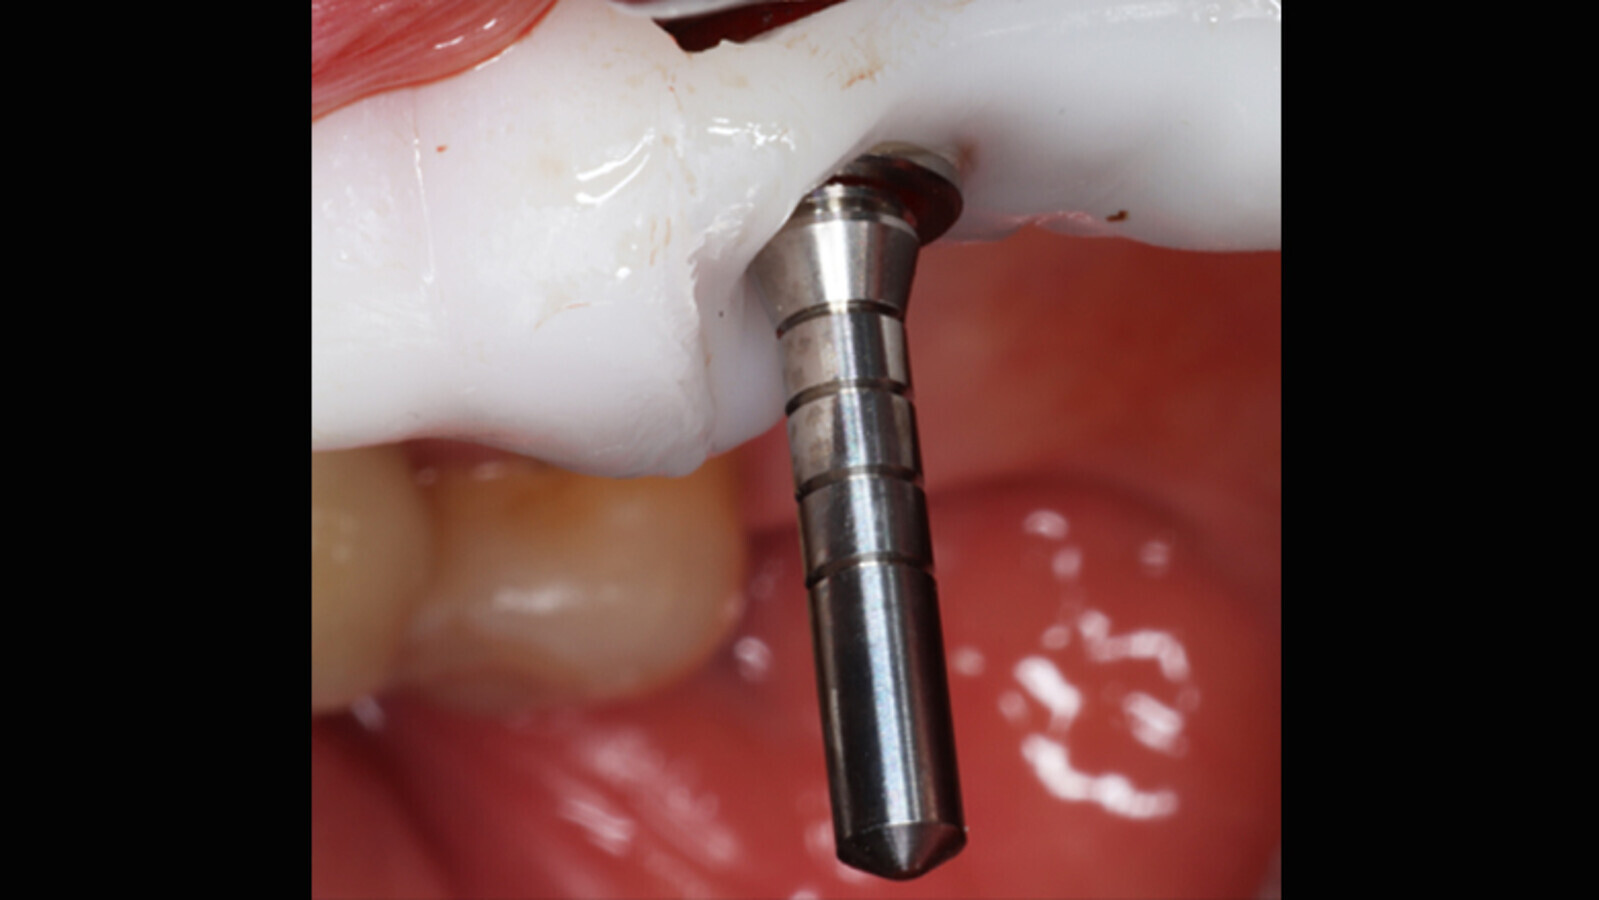

Figura 5a. Cirugía con la guía quirúrgica y colocación del implante.

Figura 5b. Cirugía con la guía quirúrgica y colocación del implante.

Figura 5c. Cirugía con la guía quirúrgica y colocación del implante.